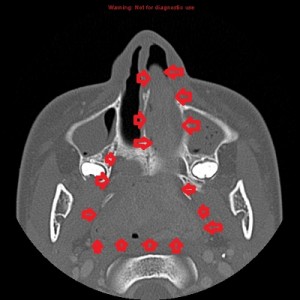

Second panel, left to right: The same set of images as in the first panel, but in bone window, showing bowing of the medial wall of the left maxillary sinus and opacified maxillary sinuses. There is no bone destruction or invasion.

Third panel, left to right: The first 2 images are coronal sections of the face showing the mass-effect of the left nasal mass on other surrounding structure.The third image in this panel is a sagittal paramedian section showing obstruction of the nasopharynx by a soft-tissue mass.